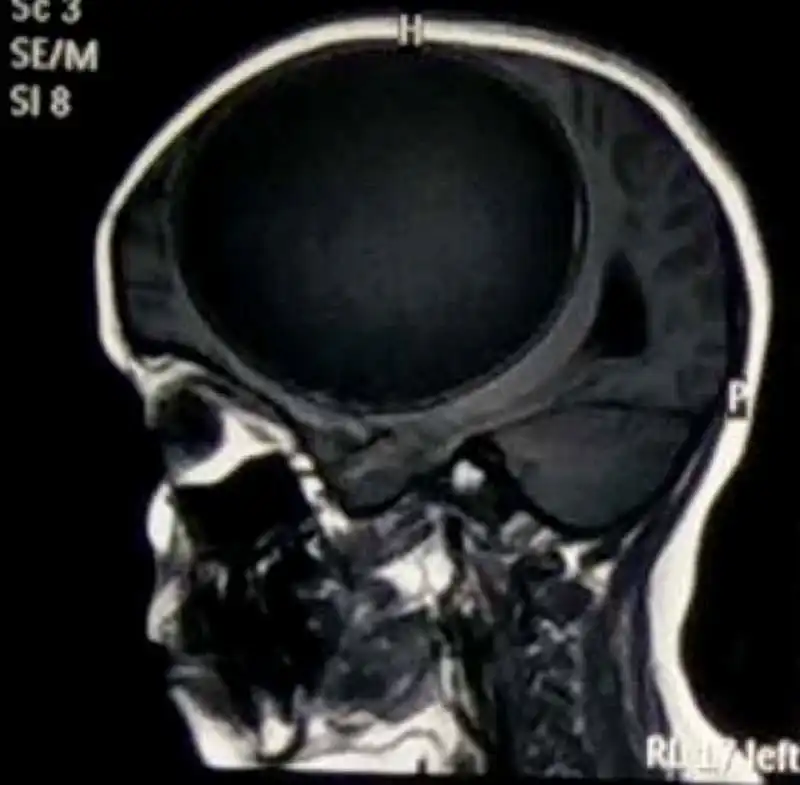

Тогда заботливый папа отвез дочь к нейрохирургу в Гандхидхам. Там и обнаружилось, что у девочки в голове развилась киста весом 675 грамм и габаритами 12,2 см x 11 см x 9,8 см. При этом никаких расстройств развития у девочки не было замечено.